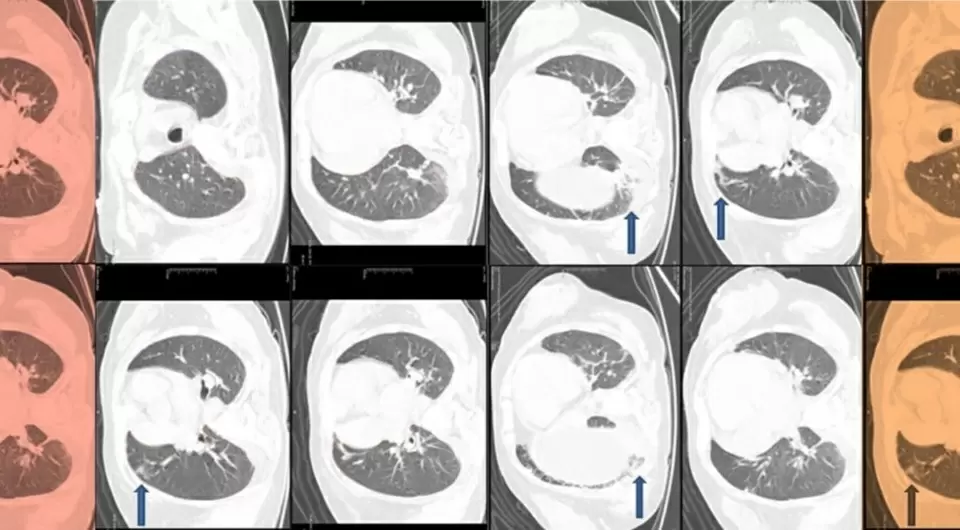

Лабораторные исследования показали панцитопению с понижением всех форменных элементов крови и выраженный дефицит витаминов B12 и D. Ультразвуковая диагностика показала увеличение печени, а компьютерная томография выявила изменения в легких, что побудило врачей больше углубиться в поиск диагнозов.